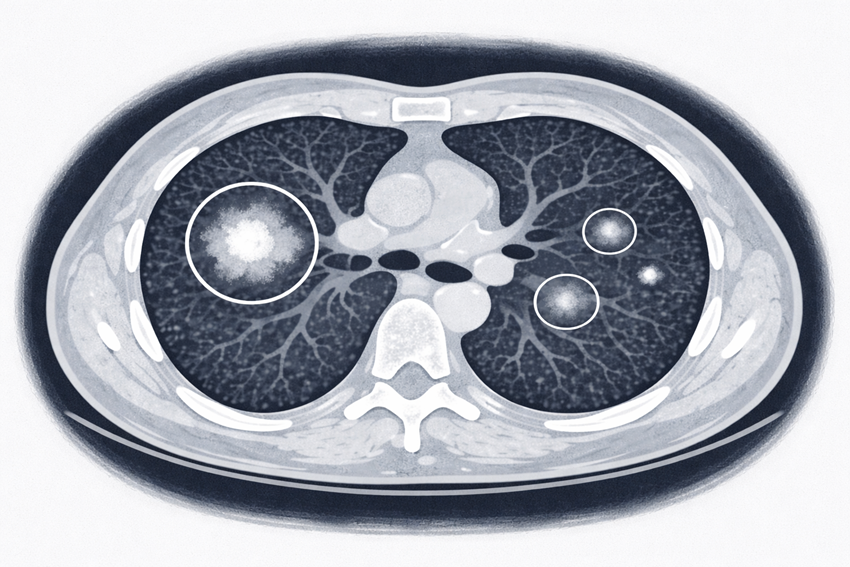

A. CT 폐암 검진과 조기 폐암 수술이 증가하면서 CT에서 반고형결절로 보이는 폐선암이 흔히 발견되고 있다. 반고형결절은 순수 간유리 결절부터 고형 성분을 동반한 병변까지 스펙트럼이 넓어, 성장 양상과 침습성 정도에 따라 임상적 의미와 예후가 달라질 수 있다. 또한 수술 전 CT에서 우세 병변 외에 동시성 반고형결절이 함께 관찰되어 총 두 개 이상의 병변으로 보이는 경우도 적지 않다.

과거에는 폐암의 전이성 병변으로 해석하기도 했으나 현재는 다중 원발성 조기 폐선암으로 보고 있다. 현행 진료 지침에서는 6mm 이상이거나 침습성이 의심되는 우세 병변을 기준으로 수술하고 나머지 결절은 추적 관찰하도록 권고하고 있다. 그러나 이러한 동시성 결절이 장기적으로 어떤 임상 경과를 보이는지, 존재 자체가 수술 후 재발이나 생존에 얼마나 영향을 미치는지에 대한 근거는 충분하지 않다. 이에 본 연구에서는 반고형결절 폐선암 수술 환자 중 동시성 반고형결절의 유무와 특성에 따른 예후 차이를 분석하고자 했다.

A. 본 연구는 임상병기 IA의 반고형결절 폐선암으로 수술받은 환자 684명을 대상으로 수술 전 CT에서 동시성 반고형결절 유무, 개수, 크기를 평가했다. 분석 결과, 동시성 반고형결절 존재 여부는 재발이나 전체 생존율과 유의한 연관성을 보이지 않았다. 즉 반고형결절이 다발성으로 존재하더라도 환자의 장기 예후가 나빠지지는 않았음을 확인한 것이다. 반면 6mm 이상인 동시성 반고형결절의 개수가 증가할수록 추적 관찰 중 추가 수술이나 국소 치료로 이어지는 2차 치료 위험은 유의하게 증가했다. 이는 동시성 결절이 환자의 생존 지표보다는 추적 관찰 과정에서 추가 치료 필요성과 더 밀접한 연관성이 있음을 시사한다.

종합하면, 반고형결절 폐선암 환자의 장기 예후는 동시성 반고형결절의 존재나 개수보다는 수술된 우세 병변의 고형 성분 크기와 병리학적 아형에 의해 주로 결정되는 것을 확인했다. 이러한 결과는 다발성 반고형결절을 동반한 환자에도 우세 병변을 중심으로 한 치료 전략이 타당하다는 것을 뒷받침한다.